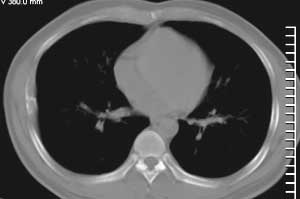

房**,38岁,间歇性胸疼2年

肋骨溶骨性破坏,皮质膨胀呈囊状,可见间隔,部分边缘硬化。考虑肋骨骨纤维结构不良。

膨胀性肋骨破坏,皮质连续。周围软组织无异常。良性占位。首先考虑骨纤。

膨胀性骨破坏,骨皮质尚完整.周围软组织脂肪间隙清楚.